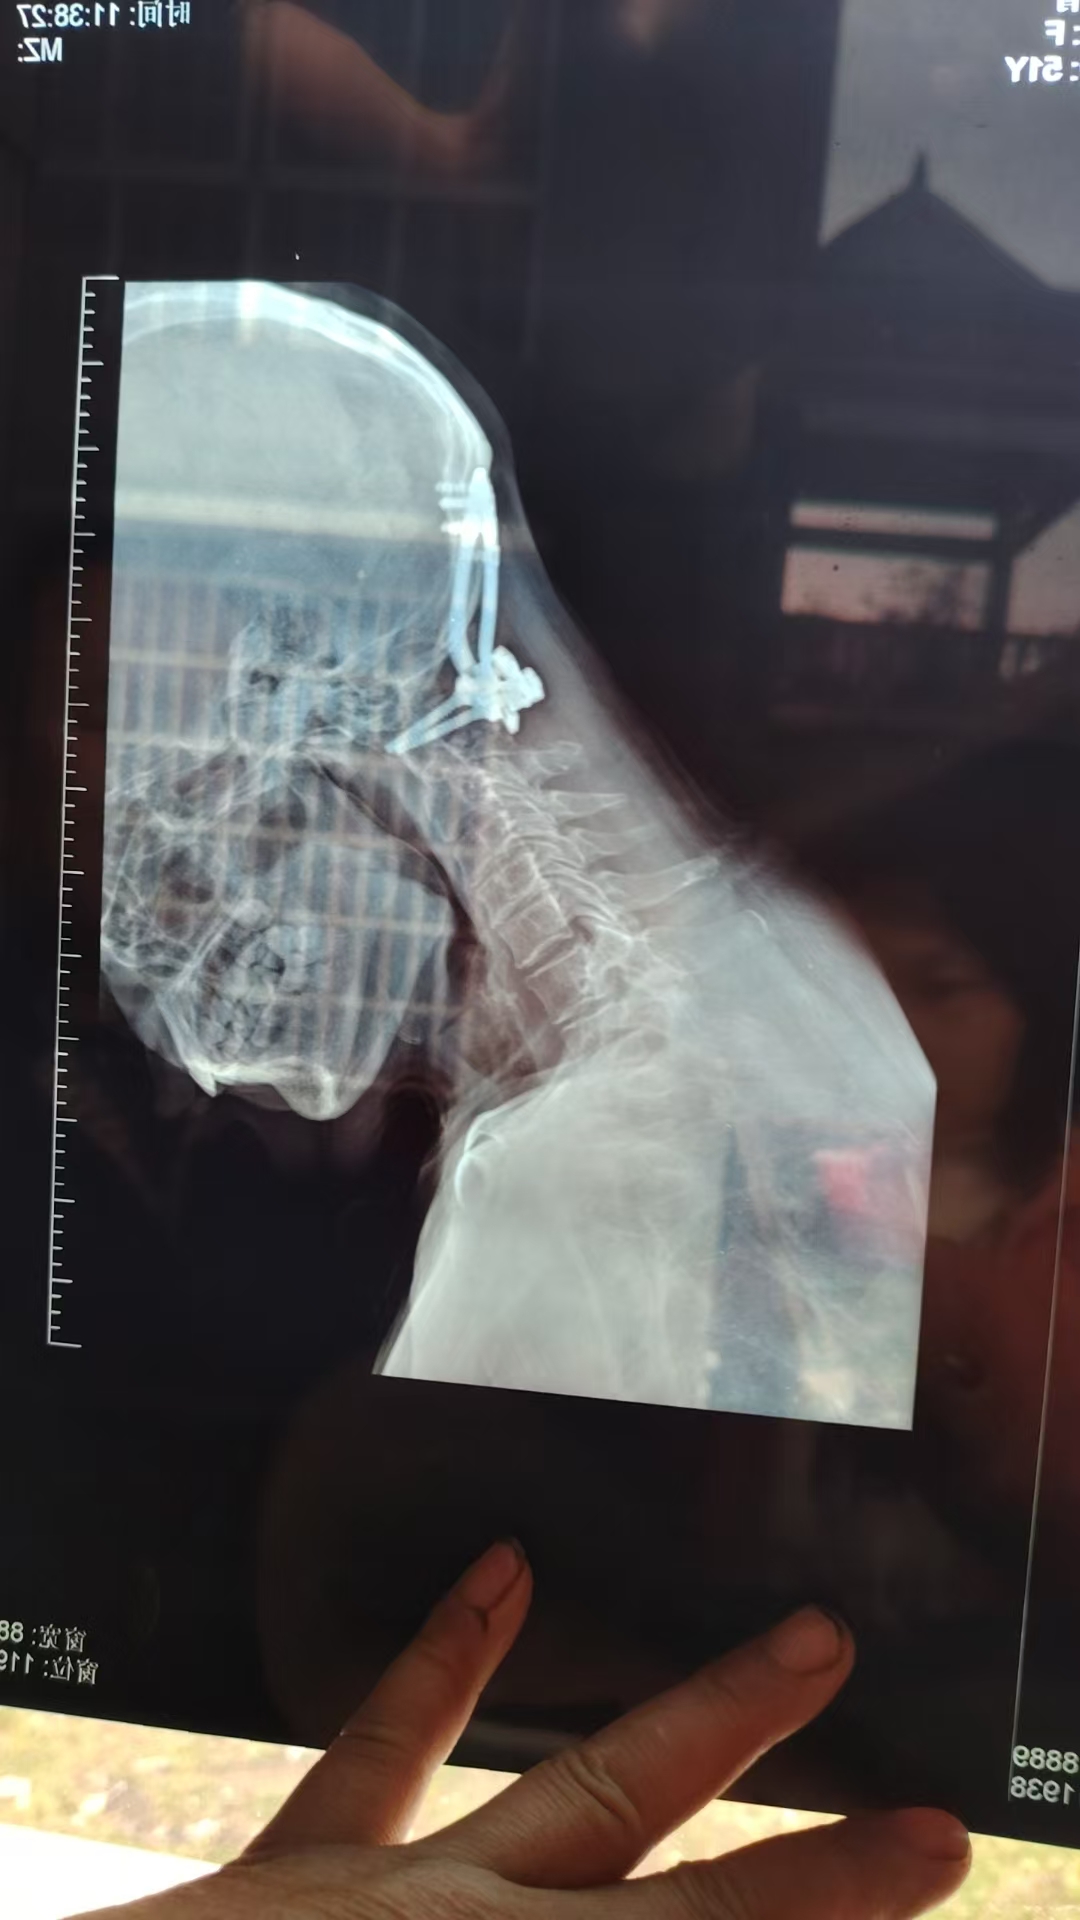

• 诊断:寰枢椎脱位

• 影像:

• 术后影像: